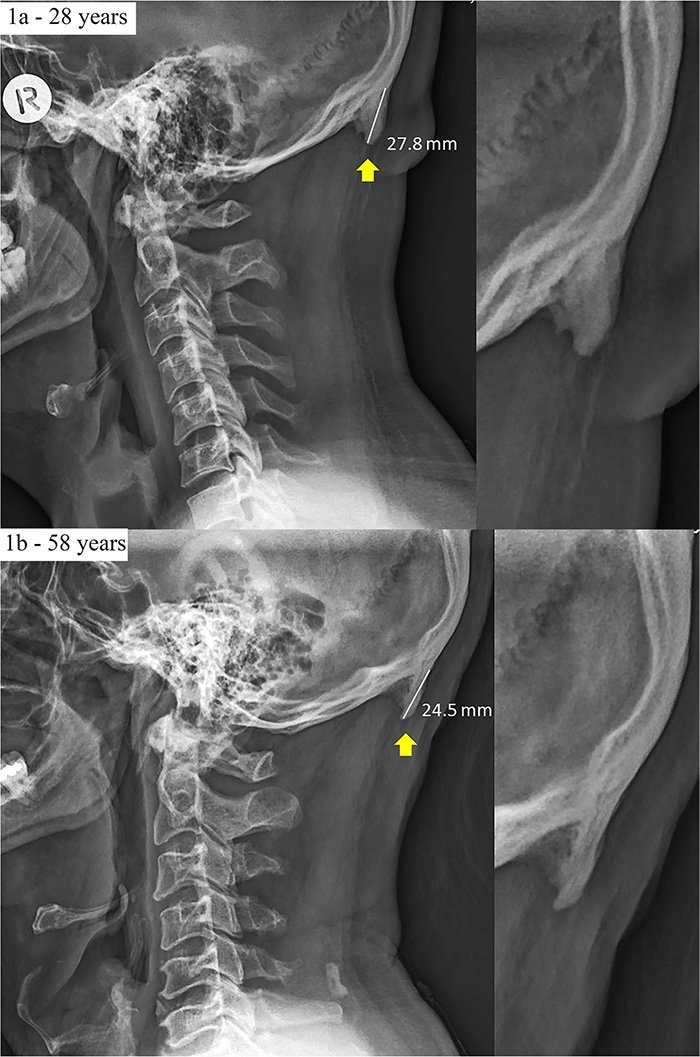

Some have been solely 10 millimetres lengthy (zero.four inches) and barely noticeable, whereas others have been as much as 30 mm in size (1.1 inches), because the scientists described of their 2018 examine.

And, whereas the common ahead head protraction recorded on this examine was 26 mm, the authors say that’s considerably bigger than what was recorded in 1996.